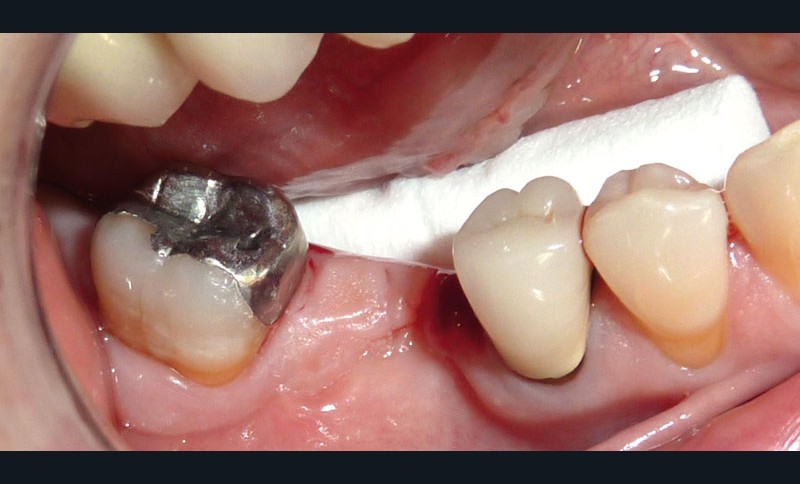

Un patient se présente pour le descellement d’un bridge 45-47 au niveau de l’onlay en 47 (fig. 1).

Afin de préserver la 45, il lui est proposé de couper le bridge en distal de 45 et en mésial de 47, de resceller l’onlay sur 47 et de poser un implant au niveau de 46, cela afin d’éviter un inévitable redescellement de la prothèse (fig. 2).